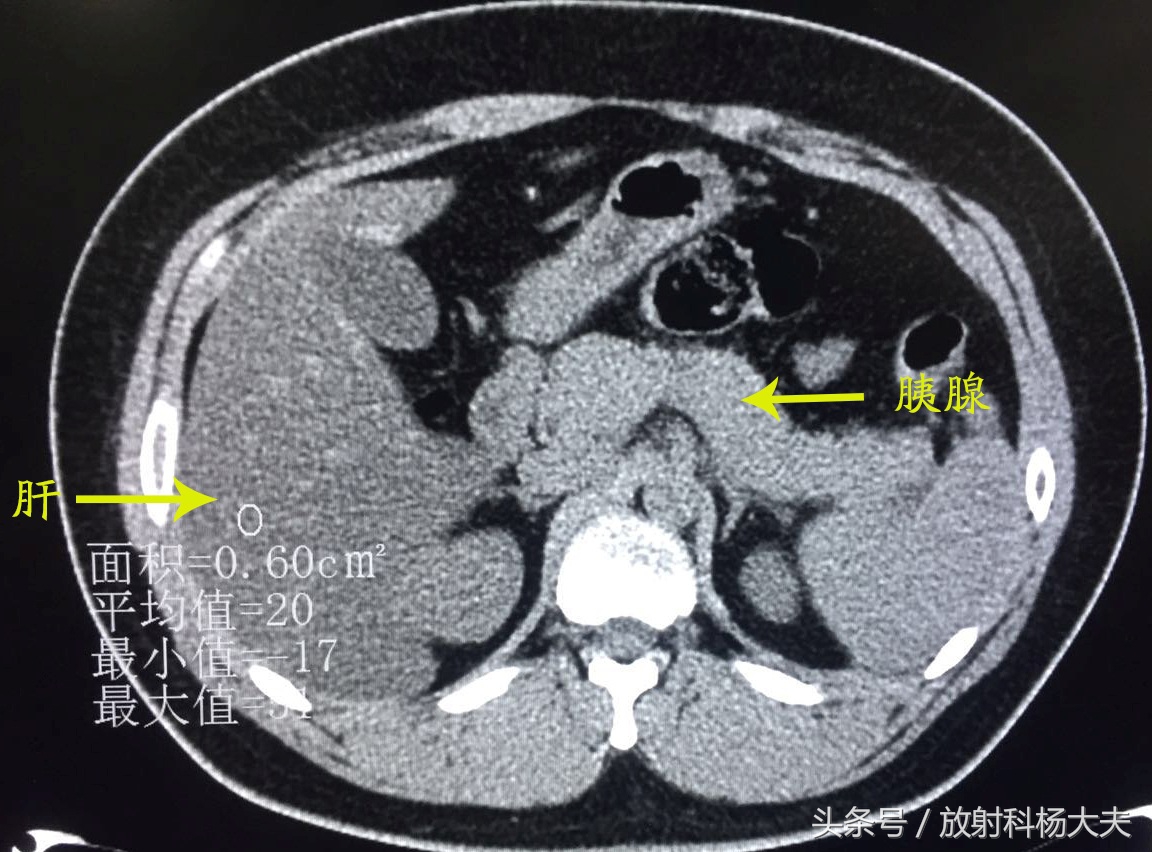

我即刻查阅了他既往的片子,果然,一年前因为腹痛就诊过,CT检查如下:

CT图像可见肝脏密度弥漫性减低,明显低于同层面脾脏密度,胰腺饱满,周围可见渗出样改变---急性胰腺炎伴重度脂肪肝。

当时治疗后复查:

胰周渗出基本吸收了,脂肪肝较前也有所好转了。